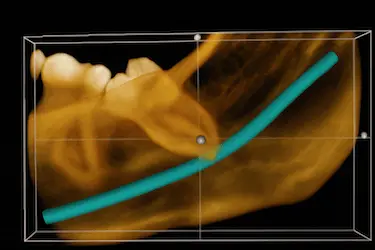

El análisis mandibular con TAC permite evitar riesgos durante la cirugía, ya que muestra la posición exacta del nervio dentario y las raíces de las muelas del juicio.

El TAC dental nos ayudará a saber cómo debemos iniciar la intervención, ya que nos mostrará cómo están ligadas las muelas del juicio a los nervios dentales y su posición exacta en la mandíbula.